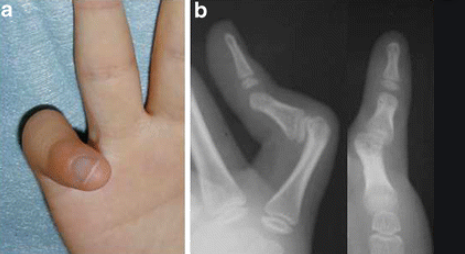

Brachydactylie: Doigts courts Polydactylie: Trop de doigts Syndactilie: Doigts fusionnés Camptodactylie: Doigts contractés Clinodactylie: Doigts inclinés Arachnodactylie: Doigts longs (comme des araignées) Amélie: Membre absent Méromélie: Membre partiellement absent Acromélie: Extrémités (Mains/Pieds) courts (=distal) Mésomélie: Avant-bras/Jambe courts (=moyen) Rhizomélie: Fémur/Humérus courts (=proximal) (Très fréquent dans les nanismes) Micromélie: Tout est court